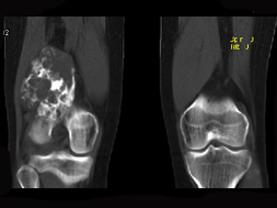

男,34岁,大腿下段疼痛2年,可摸到肿块,请结合所提供图像,选择最佳选项 ( )A、纤维肉瘤B、巨细胞瘤C、软骨肉瘤D、软骨瘤...

问题 男,34岁,大腿下段疼痛2年,可摸到肿块,请结合所提供图像,选择最佳选项 ( )

选项 A、纤维肉瘤 B、巨细胞瘤 C、软骨肉瘤 D、软骨瘤 E、骨肉瘤

答案 C